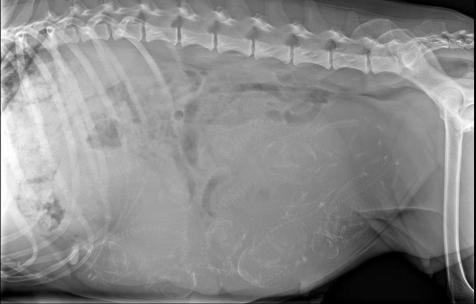

Trächtigkeitstag 53 - wir haben 12 Welpen gezählt!

Wir waren heute, an Trächtigkeitstag 53, beim röntgen und es werden (viiiiiel) mehr Welpen als erwartet. Honey muss es immer gleich so übertreiben! *lach*

Und dann folgten Stunden des warten auf Nr. 12. Honey war mit sich und den Welpen in Peace und dachte gar nicht mehr daran nochmal Wehen zu bekommen! Wie Recht sie damit hatte, sollte ich einige Zeit später in der Klinik erfahren... Beim röntgen war kein Welpe mehr zu sehen - es gibt keine Nr. 12. Erleichtert aber auch ein wenig betrübt, Honey diesen Stress aufgebürdet zu haben, sind wir alle glücklich aber erschöpft.